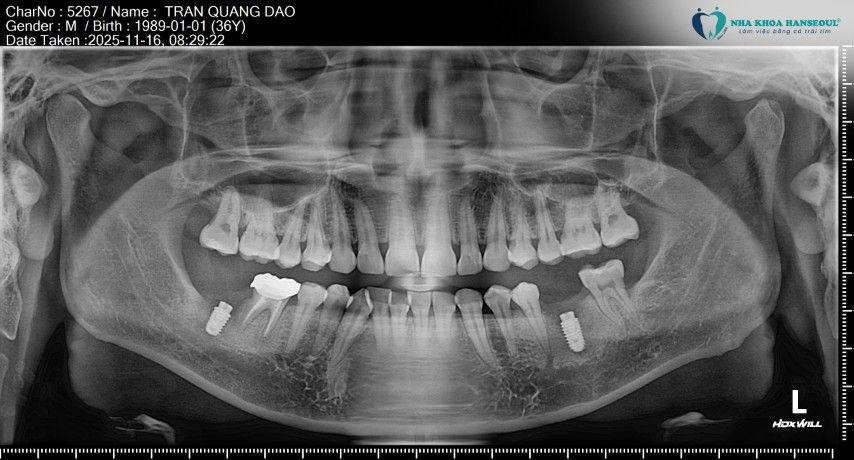

“Lúc mới làm xong thì tôi thấy ăn nhai vẫn ổn, không đau nên cũng yên tâm,” anh Đạo kể lại. Tuy nhiên, sau một thời gian, vùng răng này bắt đầu xuất hiện ổ áp xe lớn, kèm theo cảm giác đau nhức và sưng, răng bị lung lay gây ảnh hưởng tới ăn uống và sinh hoạt. Khi đến thăm khám tại Hanseoul và chụp phim CT Cone Beam, Thạc sĩ, Bác sĩ Trần Việt Hà xác định tình trạng nhiễm trùng kéo dài đã khiến xương hàm quanh chân răng bị tiêu nghiêm trọng.

Sau khi đánh giá tổng thể, bác sĩ Trần Việt Hà đã chỉ định nhổ 4 răng, bao gồm răng 36, 47 do nhiễm trùng nặng và răng khôn 18, 28 có nguy cơ gây viêm, đau và ảnh hưởng đến răng kế cận.

Với hai răng 36 và 47, bác sĩ tiến hành nhổ răng kết hợp nạo sạch ổ áp xe, làm sạch mô viêm và kiểm soát nhiễm trùng bằng kháng sinh phù hợp. Đây là bước quan trọng nhằm loại bỏ hoàn toàn vi khuẩn trước khi tiến hành cấy implant, giúp hạn chế tối đa nguy cơ biến chứng về sau.

“Lần này bác sĩ làm rất kỹ, giải thích rõ từng bước nên tôi cảm thấy yên tâm hơn nhiều,” anh Đạo nói. Sau khi vùng nhổ răng ổn định, tình trạng viêm được kiểm soát tốt, anh Đạo bước vào giai đoạn tiếp theo: cấy 2 trụ Implant tại vị trí răng 36 và 47.

Do tình trạng áp xe kéo dài trước đó, xương hàm tại vị trí răng 36 và 47 của anh Đạo đã bị tiêu xương nặng, không đủ thể tích để đặt implant một cách an toàn. Vì vậy, bác sĩ Trần Việt Hà chỉ định ghép bột xương đồng thời khi cấy implant.

_08h31.jpg)

Hai vị trí răng 36 và 47 của anh Đạo được cấy Implant Hiossen (Mỹ) – dòng implant được đánh giá cao về độ ổn định và khả năng tích hợp xương. Theo bác sĩ Trần Việt Hà, Implant Hiossen phù hợp với những ca răng hàm chịu lực nhai lớn nhờ: